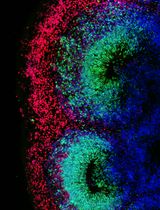

Improved Immunohistochemistry of Mouse Eye Sections Using Davidson's Fixative and Melanin Bleaching

AL Anne Nathalie Longakit

CH Chloe Hess

CZ Christina Zhang

CV Catherine D. Van Raamsdonk

1715 Views

Nov 20, 2025

Immunohistochemistry (IHC) and immunofluorescence (IF) are fundamental molecular biology techniques to assess protein expression. However, the melanin present normally in the eye in the uveal tract (choroid, iris, and ciliary body) and the retinal pigment epithelium (RPE) poses a significant challenge for IHC and IF. This is because melanin interferes with both chromogenic and fluorescent detection methods. Additionally, formalin fixation, which is commonly used for IHC, can result in shrinkage and loss of cellular detail in the eye. This protocol provides an optimized approach using Davidson’s fixative with a hydrogen peroxide bleaching step to eliminate melanin interference in the mouse eye, improving the quality and interpretability of IHC analyses of the uveal tract and RPE. It is particularly useful for the analysis of uveal melanoma.